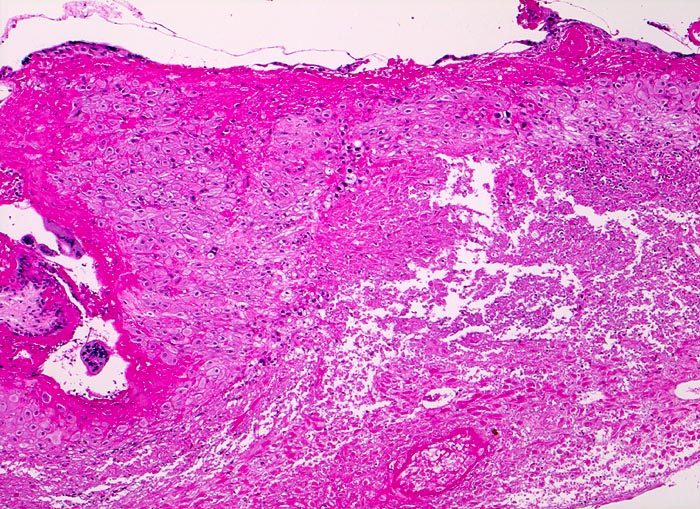

Morphologische Merkmale:

• Vergrösserte Plazentarzotten mit hydropischem Zottenstroma.

• Vereinzelt Zytotrophoblasteinschlüsse im Stroma.

• Vorwiegend einschichtiges Zytotrophoblastepithel ohne Atypien und mehrkerniger Synzytiotrophoblast. Physiologische polare Trophoblastproliferate.

• Schwangerschaftsendometrium mit hypersekretorischen sägezahnförmigen Drüsen und bizarren Kernatypien (Arias Stella Phänomen).